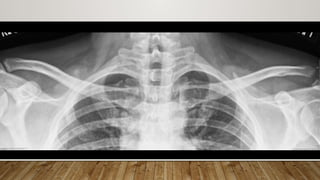

• 30 yrs/ F with history of fall from scotter

• 64Y/M with AC joint injury Type 3